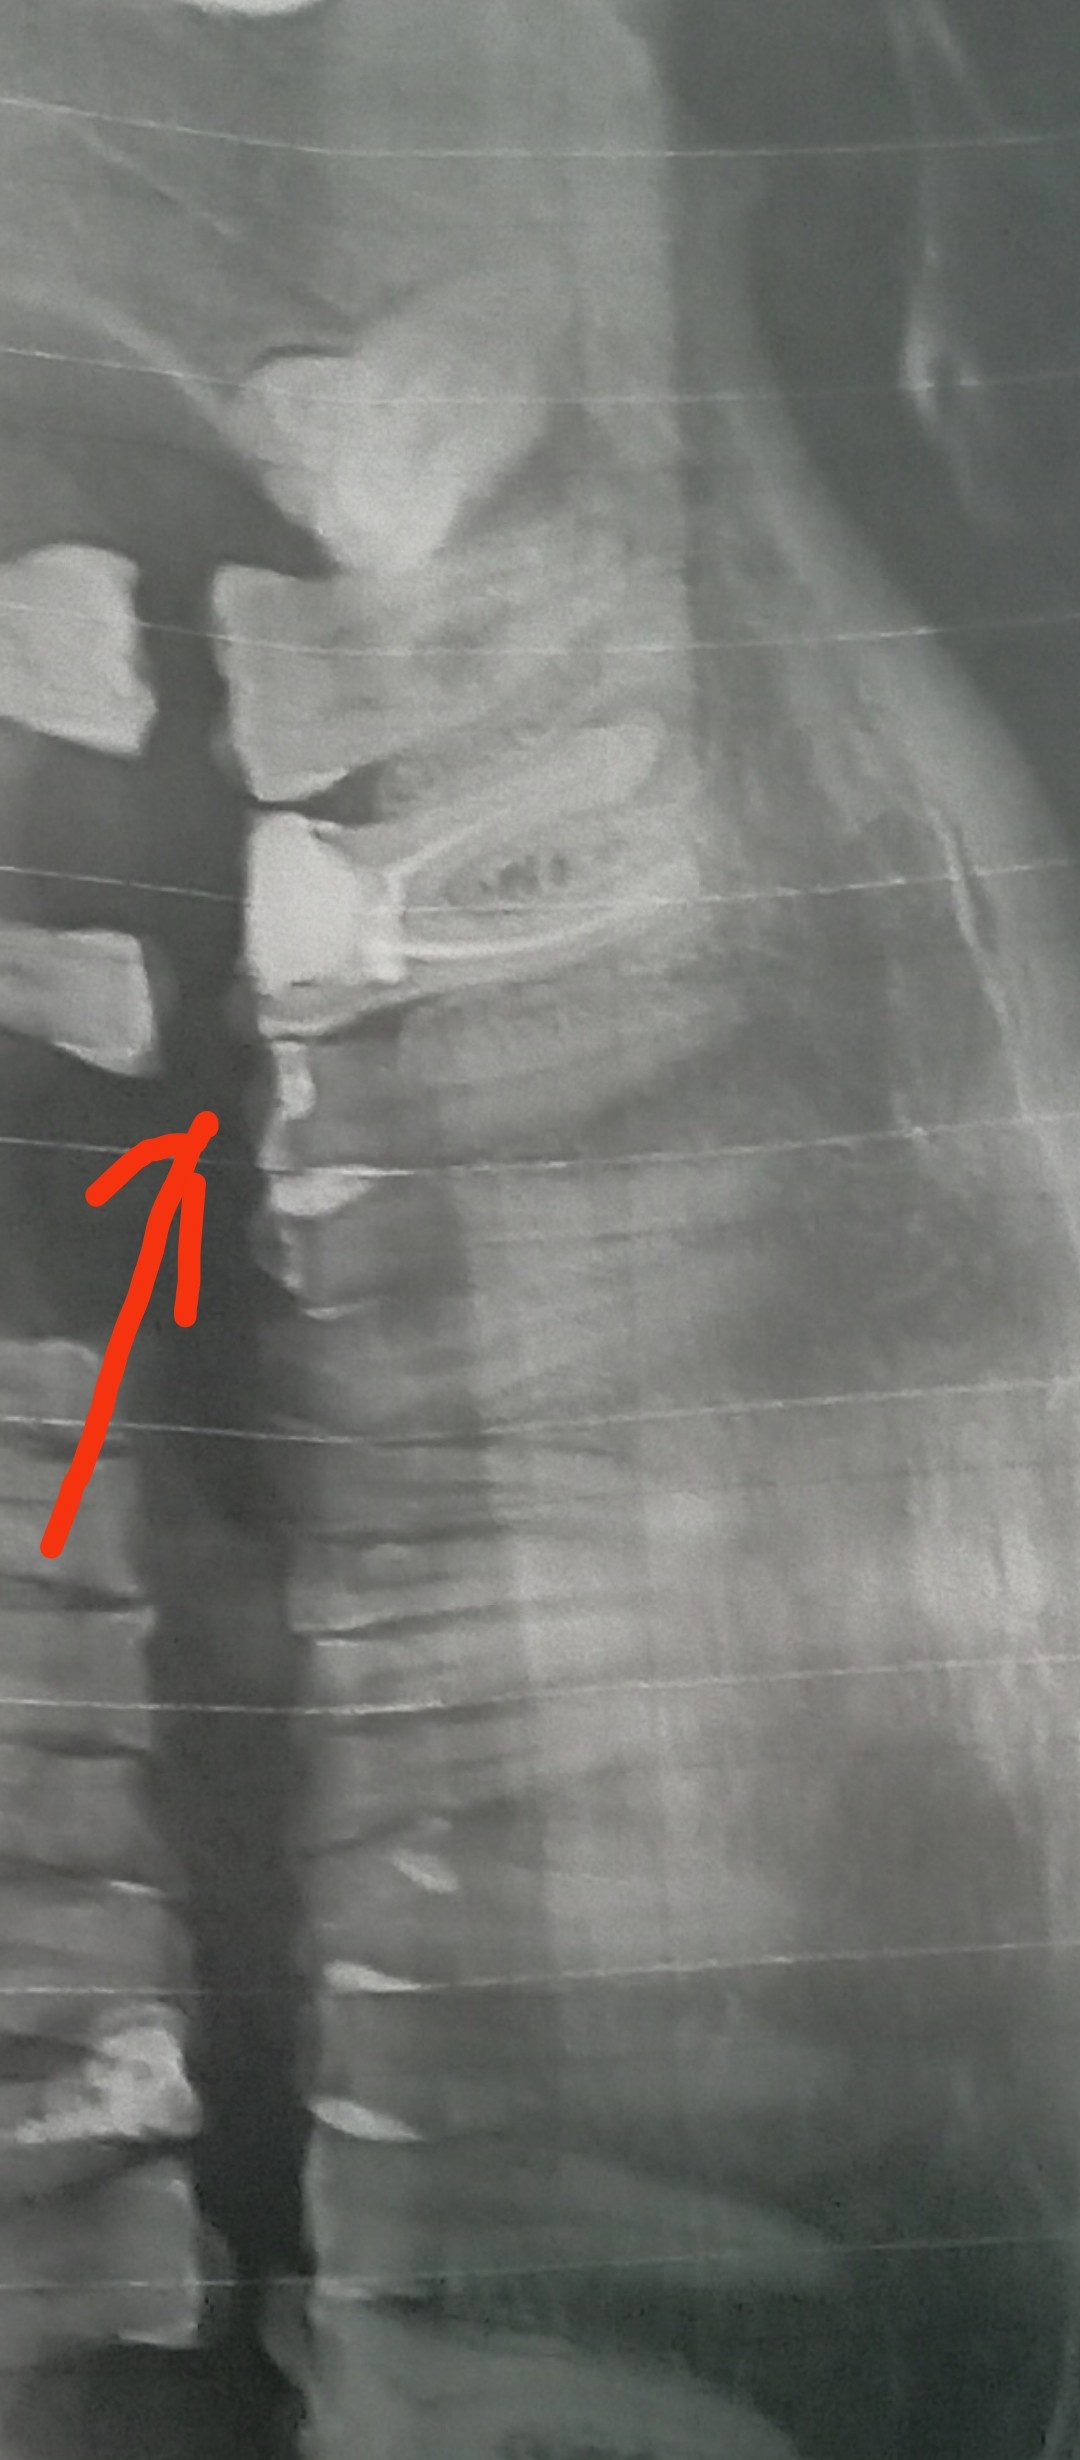

Вітаю, Добрый день. Неделю назад у меня начала болеть десна в нижнем ряду за седьмым зубом. Там как бы ранка Толи трещина и подпухло немного. Та восьмерка седит крепко. Мне 46 доктор говорил шо она уже не выйдет. Так вот через пару дней добавилась боль в шестом или седьмом зубе. Пульсирующая боль. Ночью не спал почти. Утром сегодня поехал к хирургу он удалил шестой зуб так как он плохой на снимке. Теперь я думаю решил ли я проблему, или это будет продолжаться и в е это из-за восьмёрки? Как думаете на снимке есть восполнение которое давало боль? Спасибо

"Теперь я думаю решил ли я проблему, или это будет продолжаться и в е это из-за восьмёрки? Как думаете на снимке есть восполнение которое давало боль? " - Есть воспаление, зуб удалили правильно. Но боль, которую вы испытывали, скорее всего, была связана с воспалением десны над восьмым зубом, так как всё от туда начиналось.

Я ещё не пойму что болит. Было сложное удаление. Там на снимке киста была на шестерка? А семёрка на снимке нормально?

"Там на снимке киста была на шестерка? " - Не киста, но гранулема, т. е. очаг хронического воспаления вокруг верхушки корня.

"А семёрка на снимке нормально? " - Да, нормально.

Добрый день. Позавчера был в челестно лицевой областной с сильной болью. Альвиолит. Почистили все. Выписали антибиотик моксиклав и доксициклин. Болит ужасно сильно соседний зуб пятый. Как при пульпите. На нем есть темное пятнышко но свиду зуб нормальный. Я не знаю шо делать уже с ним. Хирург сказал что зуб хороший. Но он же сильно выражено болит. Даже лунка не так болит. Как Вы видите на снимке он норм?